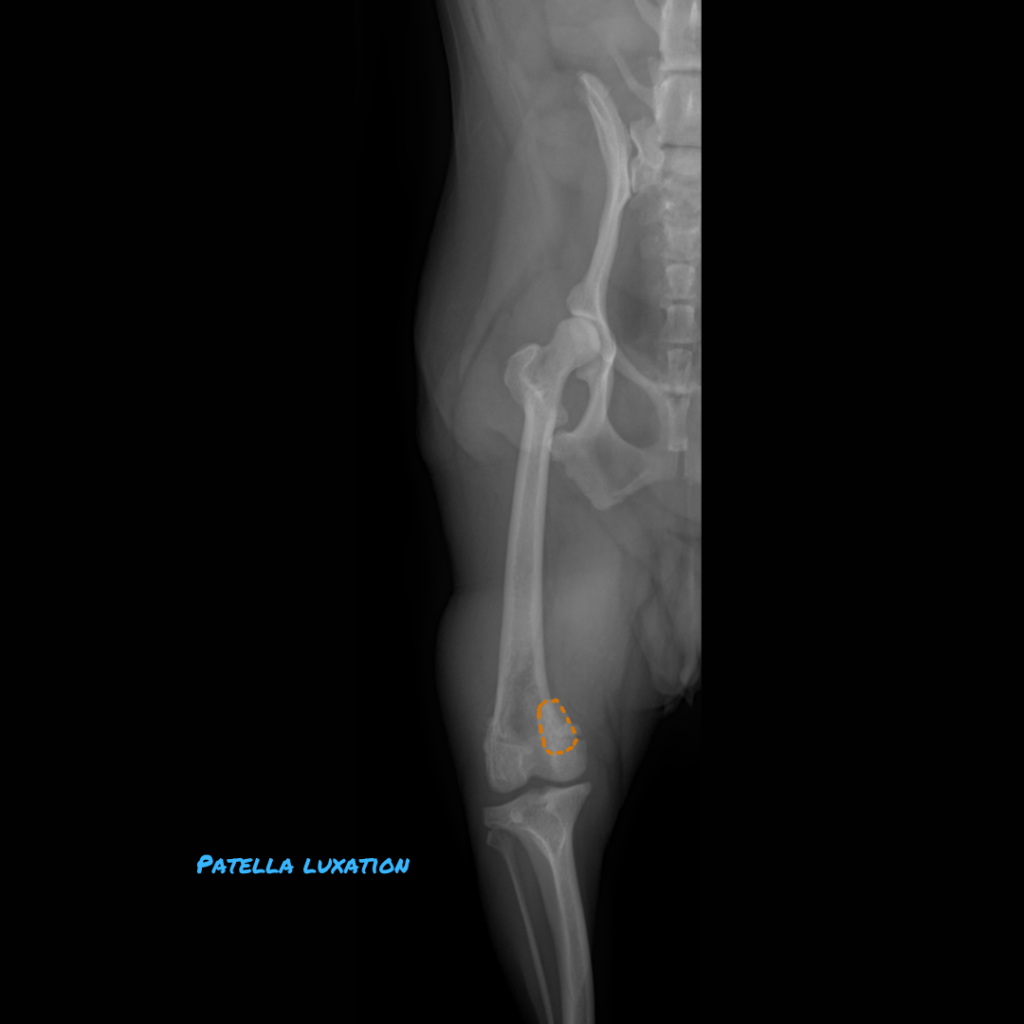

[Pic 1: The patella is highlighted with an orange dotted line and is luxated medially]